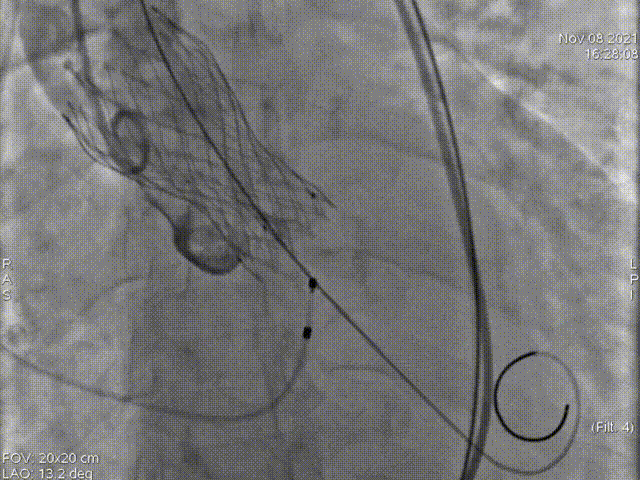

主动脉根部造影

术中多次室颤,故当机立断,不进行预扩,直接植入L26号的VenusA-Valve瓣膜。

第二次起始释放

第二次释放位置良好